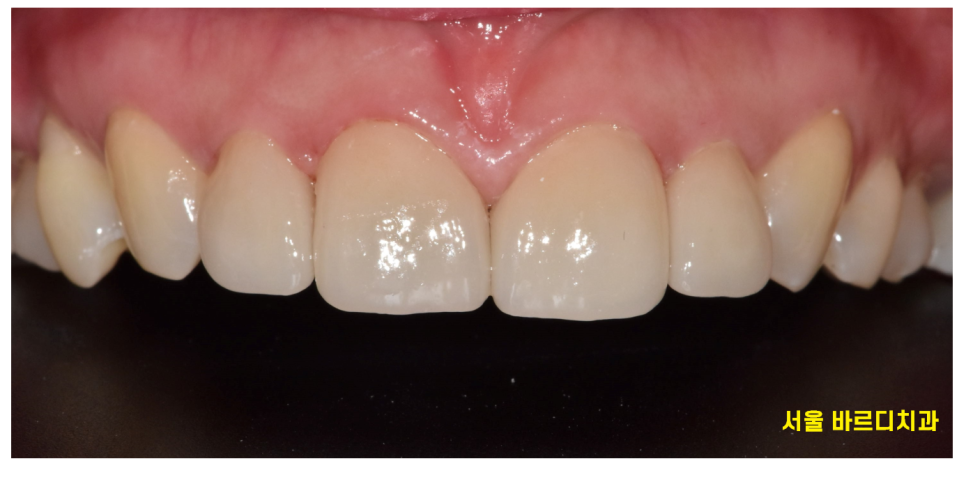

▼왜소치 라미네이트 치료결과▼

230509

어떤게 라미네이트일까요~??

감쪽같죠~??

보철이라 해서 티가 나면 안됩니다.

어떤것이 라미네이트 치아인지 감쪽같게

만들어 드리는게 기술력이죠!!!

작은 치아로 고민하시던 환자분은

앞니 4개 치아 사이즈를 재분배하여

컴플렉스 극복시켜 드렸습니다.